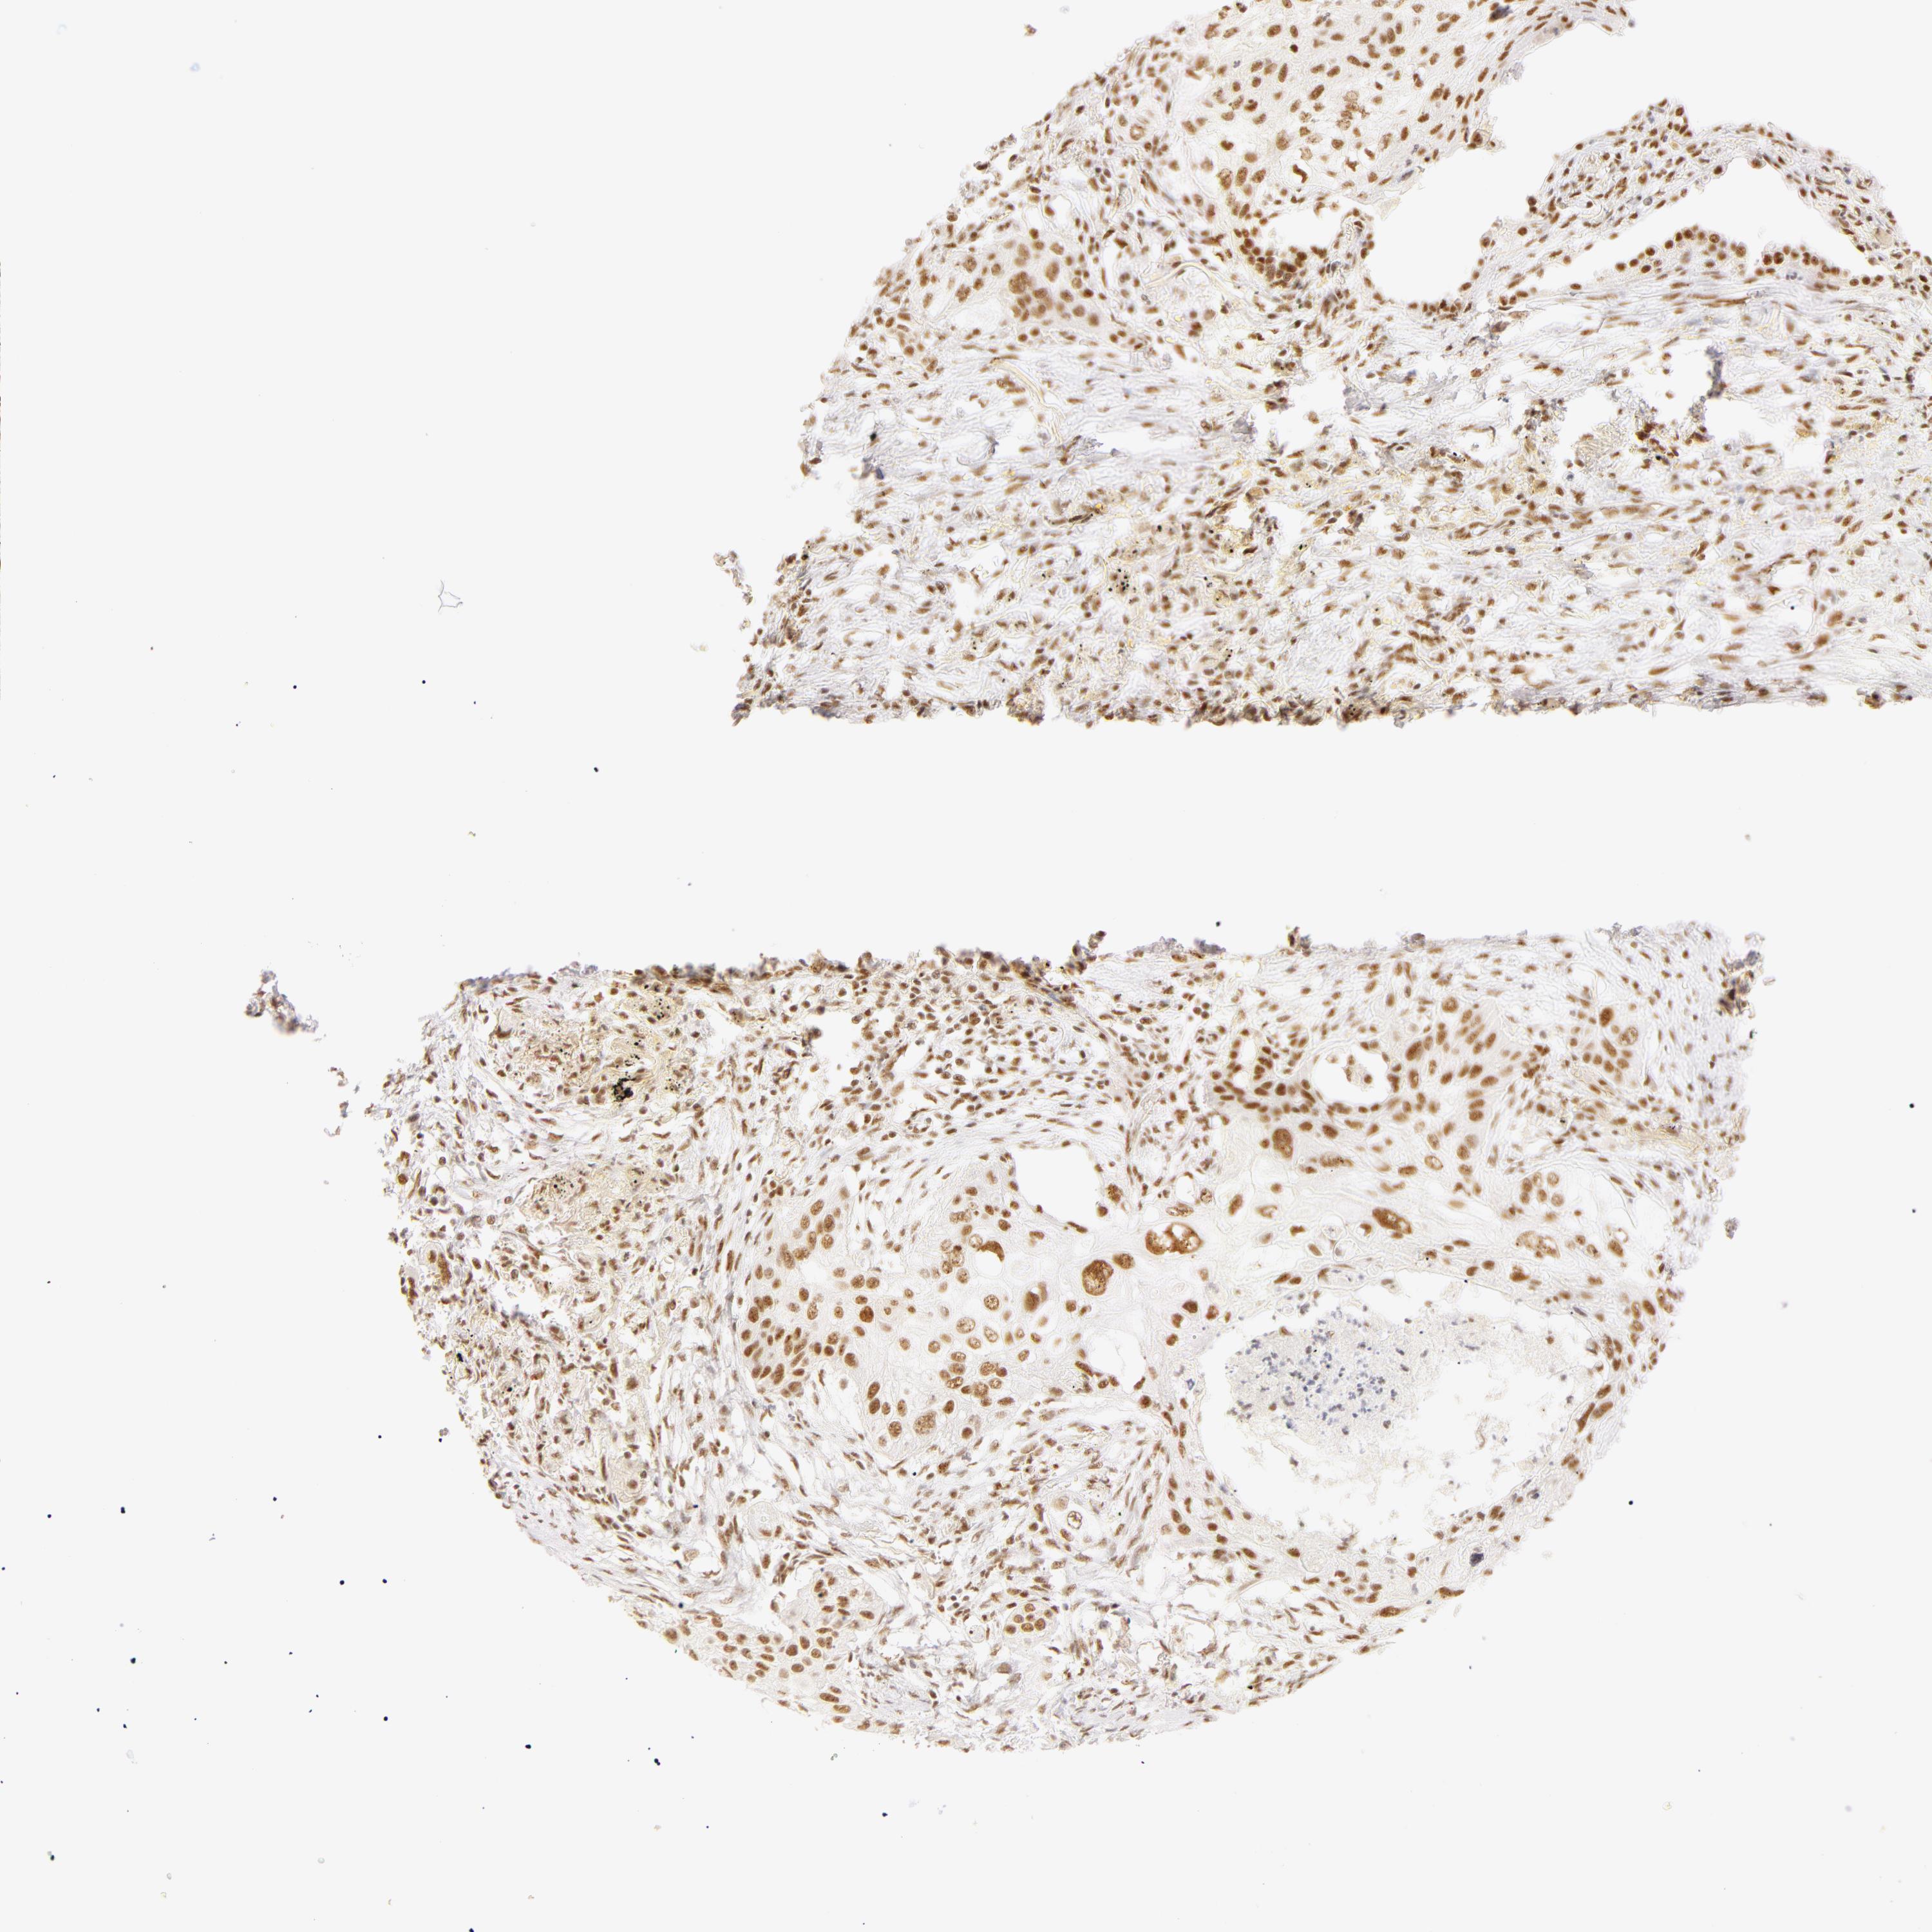

LUNG ADENOCARCINOMA (VALIDATION) - Interactive survival scatter ploti

The Survival Scatter plot shows the clinical status (i.e. dead or alive) for all individuals in the patient cohort, based on the same data that underlies the corresponding Kaplan-Meier plots. Patients that are alive at last time for follow-up are shown in blue and patients who have died during the study are shown in red.

The x-axis shows the expression levels (FPKM) of the investigated gene in the tumor tissue at the time of diagnosis. The y-axis shows the follow-up time after diagnosis (years). Both axes are complimented with kernel density curves demonstrating the data density over the axes. The top density plot shows the expression levels (FPKM) distribution among dead (red) and alive patients (blue). The right density plot shows the data density of the survived years of dead patients with high and low expression levels respectively, stratified using the cutoff indicated by the vertical dashed line through the Survival Scatter plot. This cutoff is automatically defined based on the FPKM cutoff that minimizes the p-score. The cutoff can be changed by dragging the vertical line or by entering a cutoff value in the square labeled "Current cut-off".

Under the Survival Scatter plot the p-score landscape (black curve; left axis) is shown together with dead median separation (red curve; right axis). Dead median separation is the difference in median mRNA expression between patients who have died with high and low expression, respectively. It is calculated as follows: median FPKM expression of dead patients with high expression - median FPKM expression of dead patients with low expression. This is intended to aid the user in visually exploring custom cutoffs and the associated p-scores and dead median separation.

Individual patient data is displayed and can be filtered by clicking on one or more of the category buttons on the top of the page. Categories describing expression level and patient information include: high, low, alive, dead, female, male and tumor stages. The scale of the x-axis can be toggled between linear and log-scale by clicking on the "x log" button. Mouse-over function shows TCGA ID, patient information and mRNA expression (FPKM) for each patient.

& Survival analysisi

Kaplan-Meier plots summarize results from analysis of correlation between mRNA expression level and patient survival. Patients were divided based on level of expression into one of the two groups "low" (under cut off) or "high" (over cut off). X-axis shows time for survival (years) and y-axis shows the probability of survival, where 1.0 corresponds to 100 percent.

RBM39 is not prognostic in Lung Adenocarcinoma (validation)

: 47.28

P scorei

N/A

Average pTPM 40.9

Number of samples 105